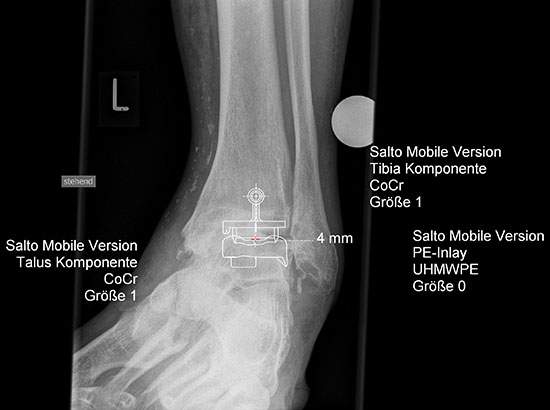

Planung einer Prothesenversorgung am oberen Sprunggelenk.

Abbildung 6